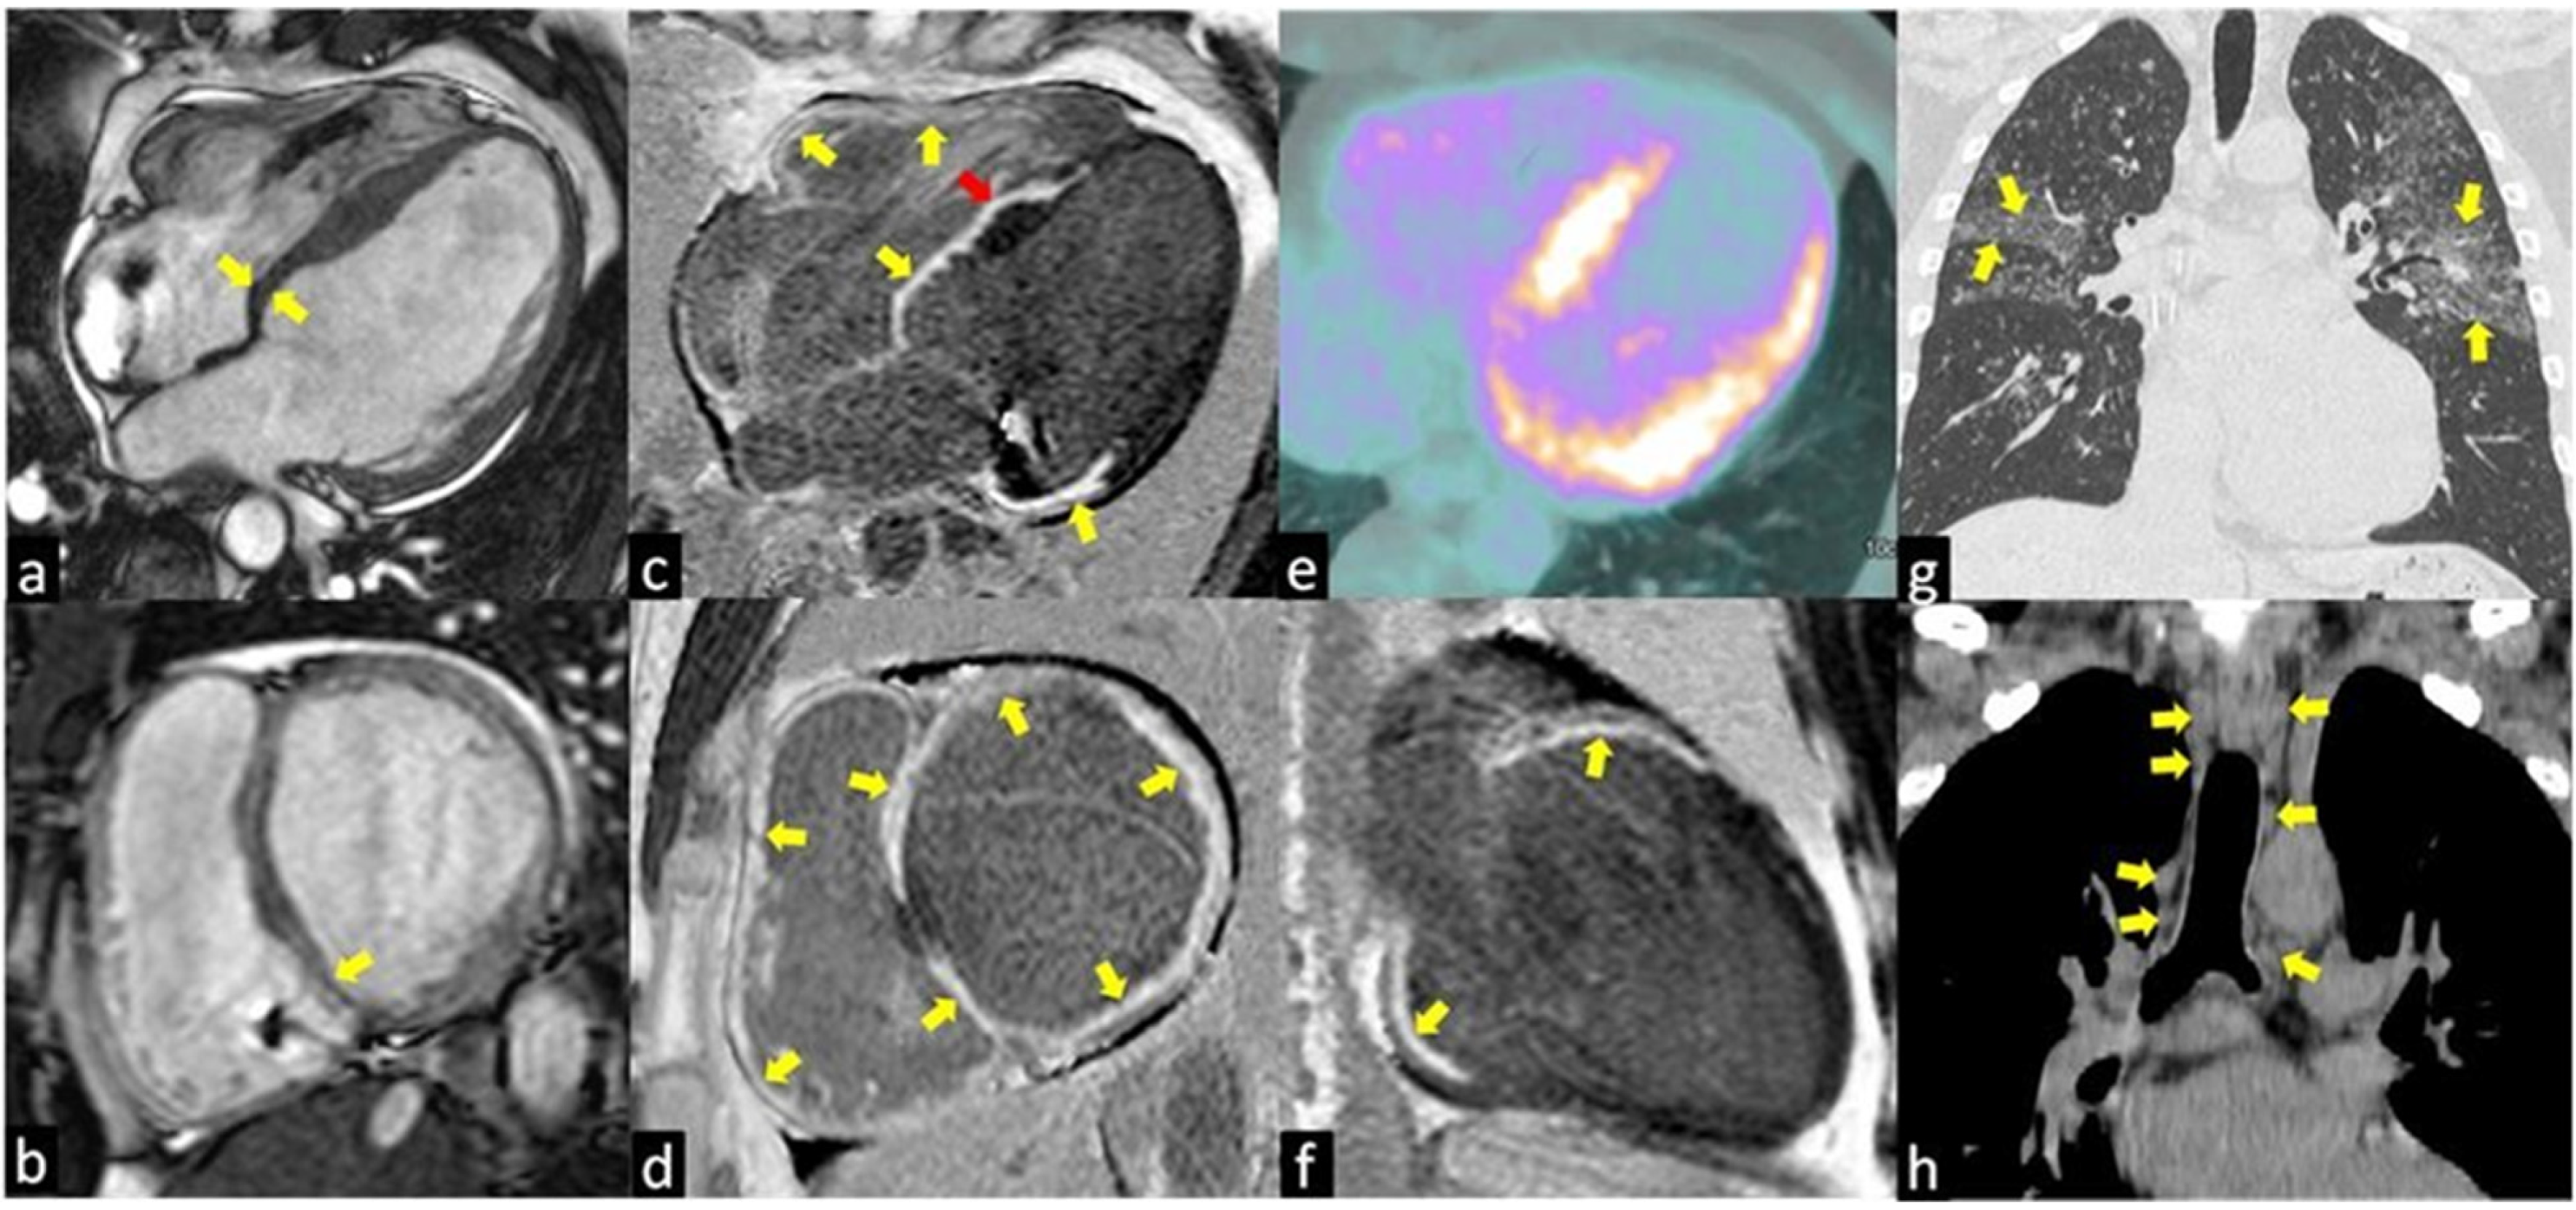

3.2. Cardiac MRI

4. 18F-FDG PET Study of Cardiac Sarcoidosis

4.1. Hybrid PET/CMR Imaging